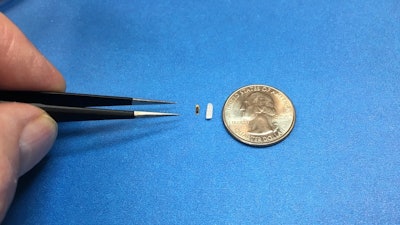

When designing an implantable device, the primary goals are functionality, durability, and minimal invasiveness. The IOP-Connect™ sensor, which measures just 4mm in length and 1.5mm in diameter, is specifically engineered to continuously monitor the pressure inside the eye, critical for patients suffering from glaucoma.

- Miniaturization: Implantable devices must be small enough to minimize trauma during implantation and avoid interfering with the body's normal functions. IOP-Connect's small form factor—achieved through advanced microfabrication techniques—ensures minimal invasiveness. This is particularly critical for ocular implants where space is limited, and precision is key. The miniaturization is enabled by leveraging silicon-based pressure sensing technology, which allows for precise, accurate measurements of absolute pressure while maintaining a small footprint, essential for integration within the eye's delicate structures.